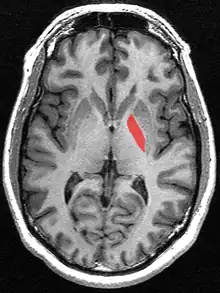

![]() Globus pallidus (in red) shown within the brain | |

The globus pallidus (GP), also known as paleostriatum or dorsal pallidum,[1] is a subcortical structure of the brain. It consists of two adjacent segments, one external, known in rodents simply as the globus pallidus, and one internal, known in rodents as the entopeduncular nucleus. It is part of the telencephalon, but retains close functional ties with the subthalamus in the diencephalon – both of which are part of the extrapyramidal motor system.[2] The globus pallidus is a major component of the basal ganglia, with principal inputs from the striatum, and principal direct outputs to the thalamus and the substantia nigra. The latter is made up of similar neuronal elements, has similar afferents from the striatum, similar projections to the thalamus, and has a similar synaptology. Neither receives direct cortical afferents, and both receive substantial additional inputs from the intralaminar thalamus.